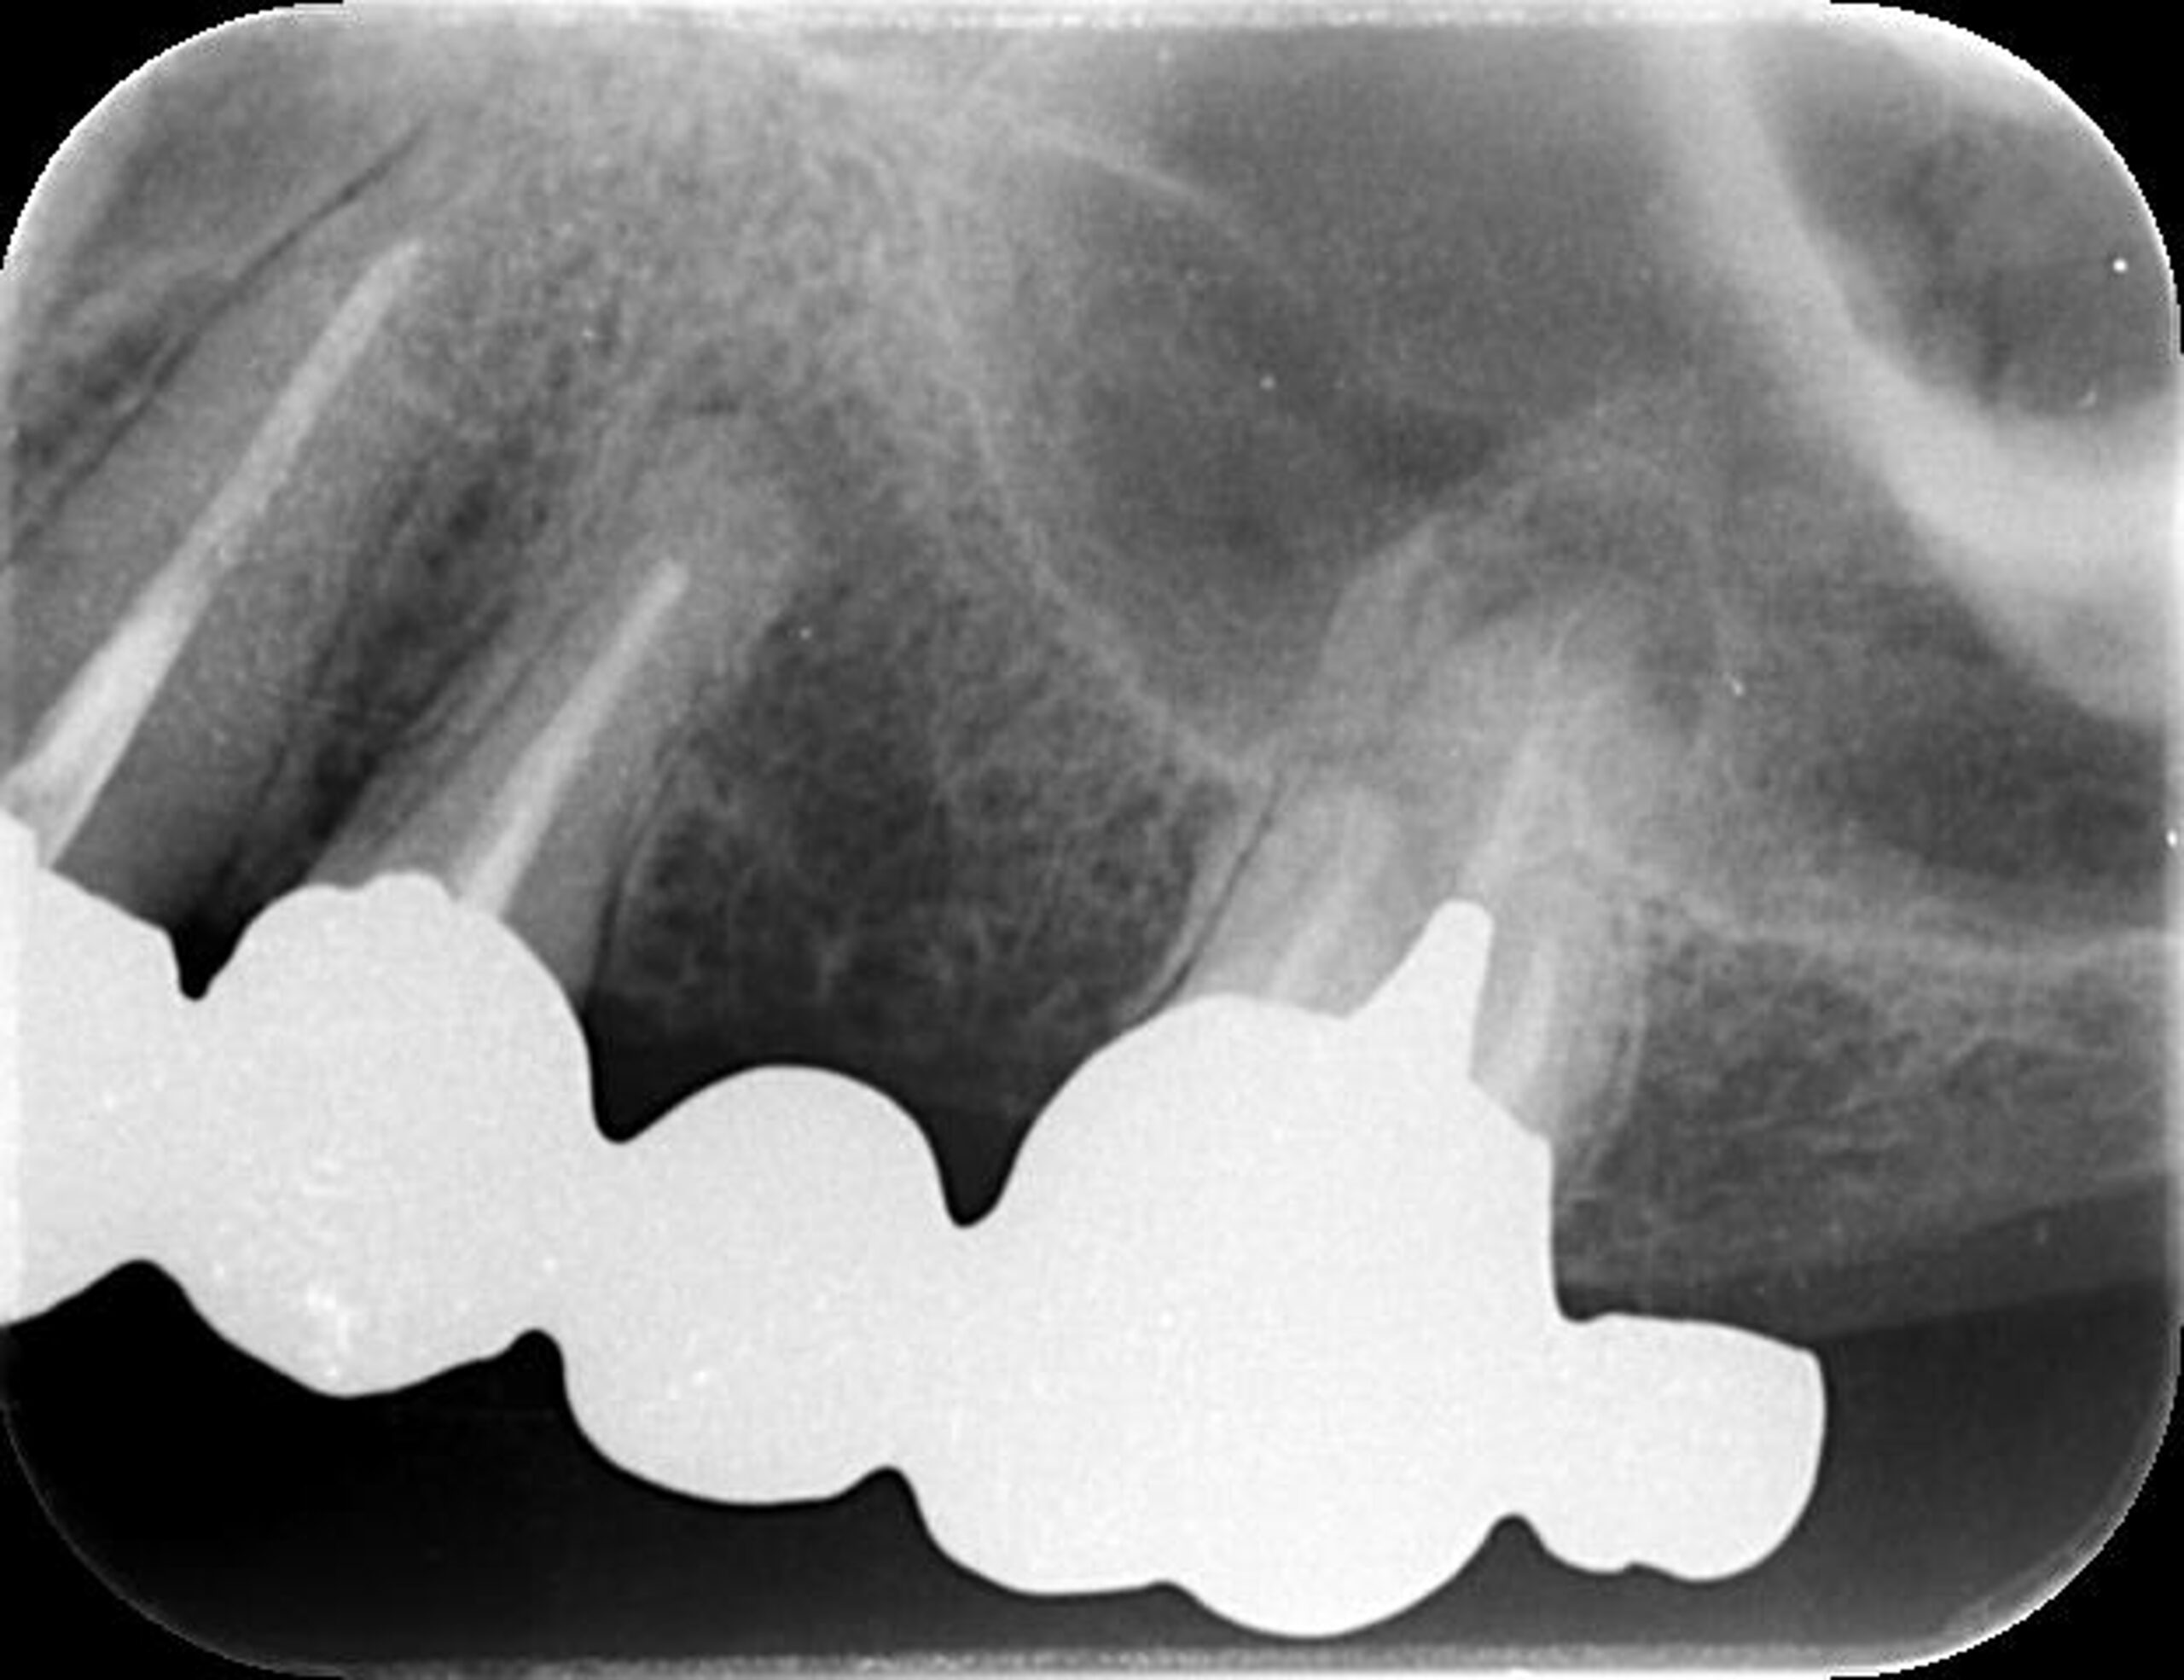

症例7

| 項目 | 詳細 |

|---|---|

| 患者様データ | 50代 男性 |

| 来院時の主訴 | 「右上の歯が噛むと少し痛い。」 |

| 医院の診断 |

虫歯の再発、未処置根管の存在 |

| 通院期間 | 4か月 |

| 来院回数 | 5回 |

| 治療費 | 220,000円(税抜) 《内訳》 精密感染根管治療80,000円、ファイバーポストコア20,000円、セラミック治療120,000円 |

| リスクと副作用 | ①根管治療歯は長期的には破折するリスク ②メインテナンスが必要 |

| ココがこだわりのポイント☝ |

上顎の小臼歯は1根か2根が通常ですが、この歯の場合なんと3根!それも途中で分岐しており4根管ありました。 これはかなりの確率で1%未満と思われます・・・術前のCT検査で発見されました。 そんな歯をラバーダム防湿とマイクロスコープを使用して丁寧に治療を行いました。 再根管治療のため、殺菌性があり歯を補強することのできる根管充填材料を使用しています。 |